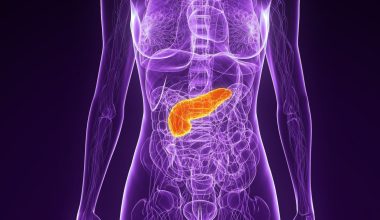

Στις περισσότερες περιπτώσεις, το πνευμονικό οίδημα οφείλεται σε καρδιακά προβλήματα.

Αλλά υγρό στον πνεύμονα μπορεί να συσσωρευθεί και για άλλους λόγους, συμπεριλαμβανομένης της πνευμονίας, της έκθεσης σε ορισμένες τοξίνες και φάρμακα, ενός τραύματος στο θωρακικό τοίχωμα, την έντονη σωματική άσκηση ή την μόνιμη διαβίωση σε μεγάλα υψόμετρα.

Πνευμονικό οίδημα είναι μια κατάσταση που προκαλείται από την συσσώρευση υγρού στους πνεύμονες.

Αυτό το υγρό συλλέγεται στους πολυάριθμους θύλακες αέρα στους πνεύμονες, καθιστώντας δύσκολη την αναπνοή.

Το πνευμονικό οίδημα που αναπτύσσεται ξαφνικά (οξύ) είναι μια επείγουσα ιατρική κατάσταση που απαιτεί άμεση περίθαλψη.

Αν και η πάθηση μερικές φορές μπορεί να αποδειχθεί μοιραία για την ζωή του ασθενούς, οι προοπτικές βελτιώνονται, όταν λάβει άμεση θεραπεία τόσο για την ίδια την πάθηση, όσο και για το υποκείμενο πρόβλημα που την προκαλεί.